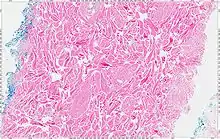

The tumors are unencapsulated and poorly circumscribed, showing a firm, white cut surface. Most tumors are about 3.5 cm, but can be up to 8 cm.[1] By microscopic examination, there are haphazardly arranged thick collagen fibers, with a low cellularity and no pleomorphism. There are usually entrapped fat cells, skeletal muscle, and peripheral nerves. The may be perineural fibrosis. The elastic fibers may be altered, which is why an elastofibroma is considered in the differential diagnosis.[1]

The tumor cells are strongly positive for vimentin, CD34, and sometimes with CD99. There is often (up to 2/3rds) a nuclear reaction with β-catenin.[1]